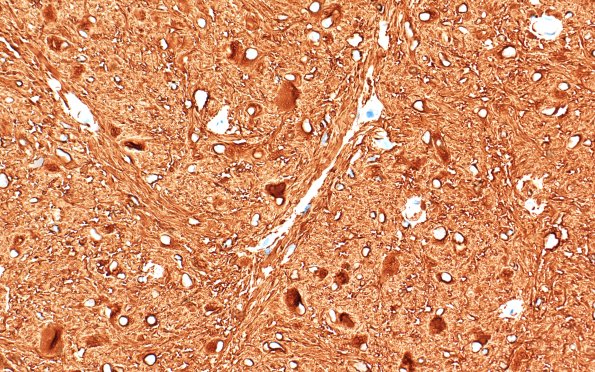

21C2-4 Both spindled cells and scattered ballooned cells are GFAP immunolabeled. (GFAP IHC)